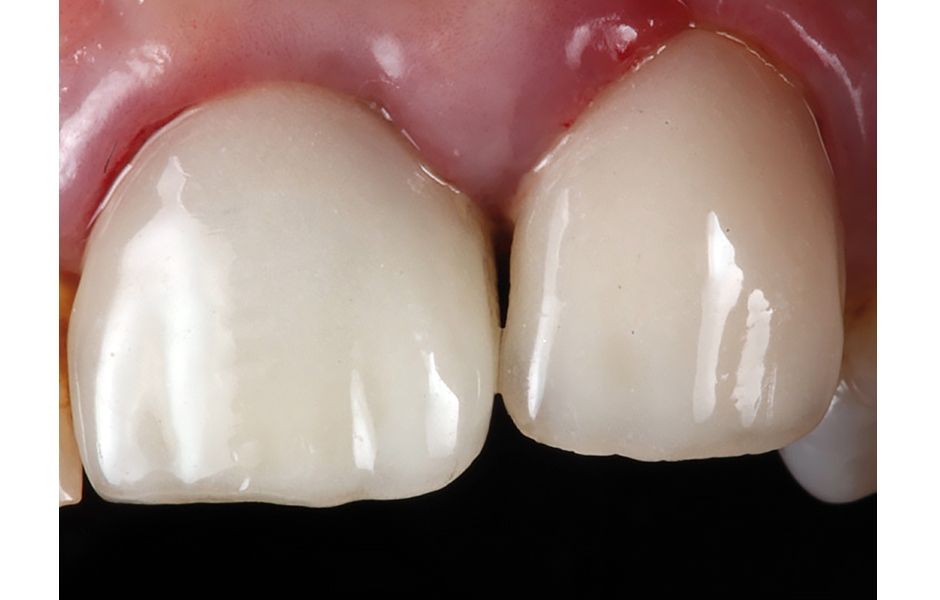

- Obr. 17: Finální zirkonové korunky byly nasazeny 3 měsíce po zavedení implantátů – snímek zachycuje situaci 1 rok po operaci.